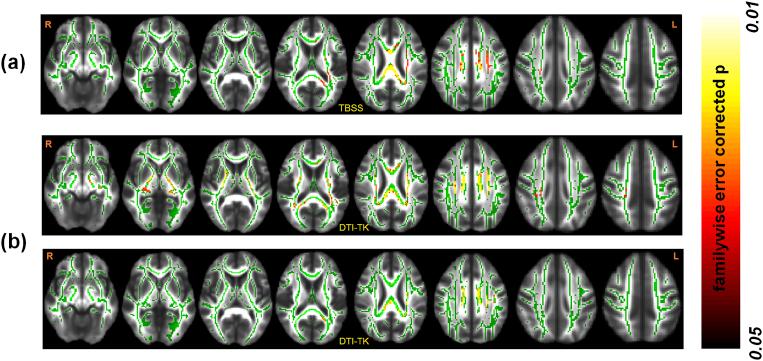

Diffusion tensor imaging (DTI) studies in early Parkinson's disease (PD) to understand pathologic changes in white matter (WM) organization are variable in their findings. Evaluation of different analytic techniques frequently employed to understand the DTI-derived change in WM organization in a multisite, well-characterized, early stage PD cohort should aid the identification of the most robust analytic techniques to be used to investigate WM pathology in this disease, an important unmet need in the field. Thus, region of interest (ROI)-based analysis, voxel-based morphometry (VBM) analysis with varying spatial smoothing, and the two most widely used skeletonwise approaches (tract-based spatial statistics, TBSS, and tensor-based registration, DTI-TK) were evaluated in a DTI dataset of early PD and Healthy Controls (HC) from the Parkinson's Progression Markers Initiative (PPMI) cohort. Statistical tests on the DTI-derived metrics were conducted using a nonparametric approach from this cohort of early PD, after rigorously controlling for motion and signal artifacts during DTI scan which are frequent confounds in this disease population. Both TBSS and DTI-TK revealed a significantly negative correlation of fractional anisotropy (FA) with disease duration. However, only DTI-TK revealed radial diffusivity (RD) to be driving this FA correlation with disease duration. HC had a significantly positive correlation of MD with cumulative DaT score in the right middle-frontal cortex after a minimum smoothing level (at least 13mm) was attained. The present study found that scalar DTI-derived measures such as FA, MD, and RD should be used as imaging biomarkers with caution in early PD as the conclusions derived from them are heavily dependent on the choice of the analysis used. This study further demonstrated DTI-TK may be used to understand changes in DTI-derived measures with disease progression as it was found to be more accurate than TBSS. In addition, no singular region was identified that could explain both disease duration and severity in early PD. The results of this study should help standardize the utilization of DTI-derived measures in PD in an effort to improve comparability across studies and time, and to minimize variability in reported results due to variation in techniques.

在早期帕金森病(PD)中,利用扩散张量成像(DTI)研究来了解白质(WM)结构的病理变化,其研究结果存在差异。在一个多中心、特征明确的早期PD队列中,评估常用于理解DTI衍生的WM结构变化的不同分析技术,应有助于确定用于研究该疾病WM病理学的最可靠分析技术,这是该领域一个尚未满足的重要需求。因此,在帕金森病进展标志物计划(PPMI)队列的早期PD和健康对照(HC)的DTI数据集中,对基于感兴趣区域(ROI)的分析、具有不同空间平滑度的基于体素的形态学(VBM)分析以及两种最广泛使用的基于骨架的方法(基于纤维束的空间统计,TBSS,和基于张量的配准,DTI-TK)进行了评估。在严格控制DTI扫描期间的运动和信号伪影(这在该疾病人群中是常见的混淆因素)后,使用来自该早期PD队列的非参数方法对DTI衍生的指标进行统计检验。TBSS和DTI-TK均显示分数各向异性(FA)与疾病持续时间呈显著负相关。然而,只有DTI-TK显示径向扩散率(RD)驱动了这种FA与疾病持续时间的相关性。在达到最小平滑水平(至少13mm)后,HC在右侧额中回皮质中平均扩散率(MD)与累积DaT评分呈显著正相关。本研究发现,在早期PD中,应谨慎使用诸如FA、MD和RD等标量DTI衍生测量作为成像生物标志物,因为从中得出的结论在很大程度上依赖于所使用的分析方法。本研究进一步证明,DTI-TK可用于理解DTI衍生测量随疾病进展的变化,因为它比TBSS更准确。此外,未发现单一区域能够解释早期PD中的疾病持续时间和严重程度。本研究结果应有助于规范PD中DTI衍生测量的应用,以提高不同研究和时间之间的可比性,并尽量减少由于技术差异导致的报告结果的变异性。